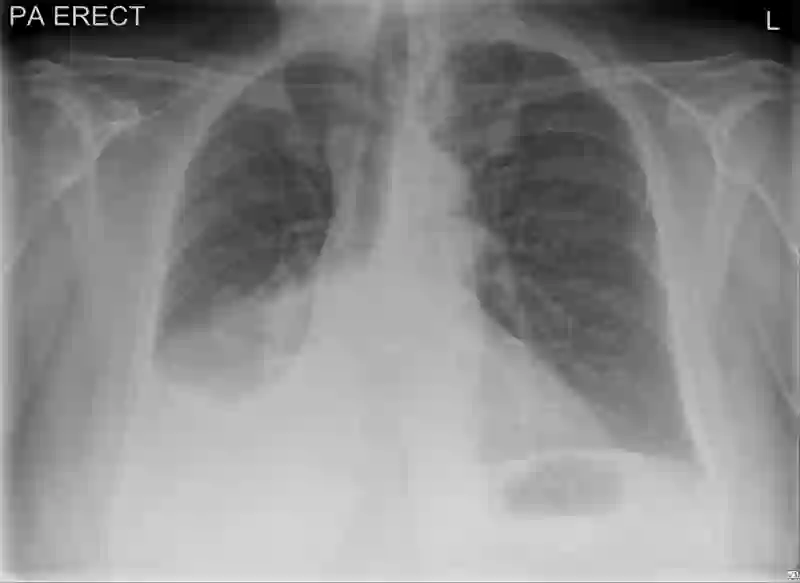

Chest radiography has been a recommended procedure for patient triaging and resource management in intensive care units (ICUs) throughout the COVID-19 pandemic. The machine learning efforts to augment this workflow have been long challenged due to deficiencies in reporting, model evaluation, and failure mode analysis. To address some of those shortcomings, we model radiological features with a human-interpretable class hierarchy that aligns with the radiological decision process. Also, we propose the use of a data-driven error analysis methodology to uncover the blind spots of our model, providing further transparency on its clinical utility. For example, our experiments show that model failures highly correlate with ICU imaging conditions and with the inherent difficulty in distinguishing certain types of radiological features. Also, our hierarchical interpretation and analysis facilitates the comparison with respect to radiologists' findings and inter-variability, which in return helps us to better assess the clinical applicability of models.